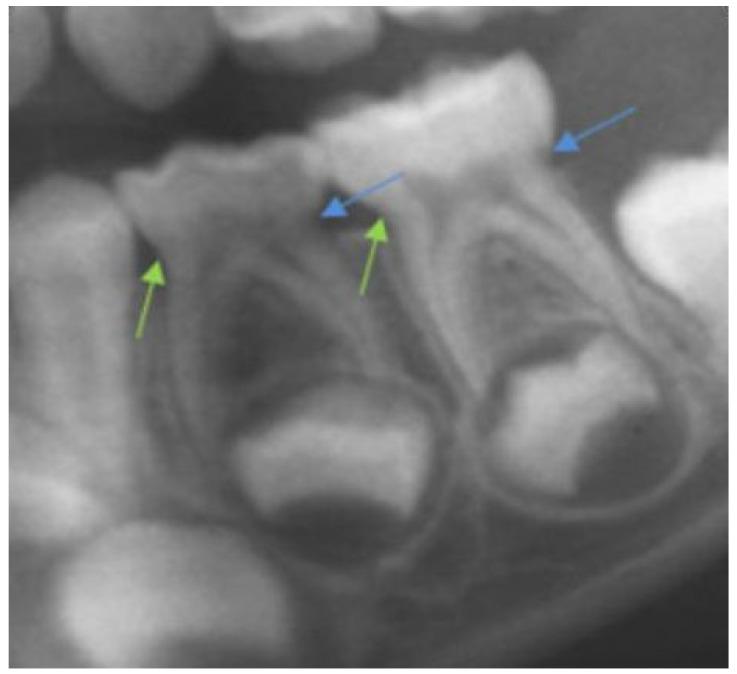

The sample consisted of 408 digital panoramic radiographs. The mesial and distal crown-to-root ratios (CRR) of #74 and #75 were calculated by dividing the measures of the length of each root by its coronal height. The Demirjian formation stage of the premolar was established, and dental age was determined. A descriptive and statistical analysis was performed using SPSS to determine the correlation between the variables (Pearson's correlation coefficient) and to identify the differences between them (Student's -test), with a confidence level of 95%.

723 molars were measured, and tables of CRR depending on dental and chronological age were obtained. The CRR decreased with increasing dental and chronological age, but not uniformly. The CRR of #74 and #75 decreased slightly when the successor premolar was in the initial stages of formation. Gender differences were obtained with respect to chronological age, mainly in girls, because the root resorption of #74 was always more advanced, and the formation of the #34 more advanced.

Root resorption of the molar is slight and progressive when the successor premolar begins formation until stage D, and becomes higher starting at stage E. It is possible to determine the state of the child's maturation and the CRR according to dental and chronological age.